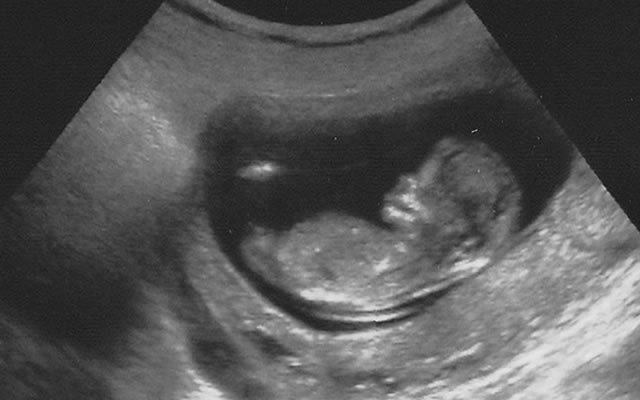

10 Haftalık Bebek Ultrason Görüntüleri